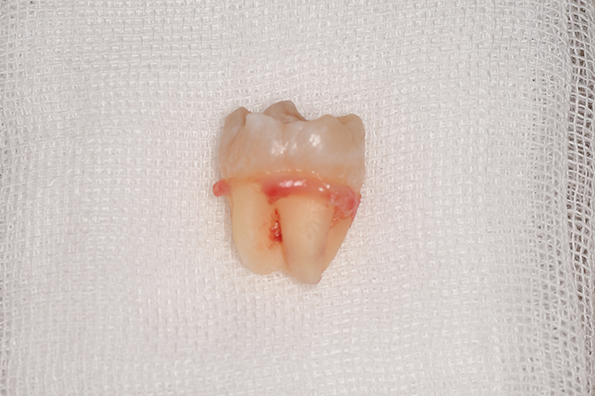

CASE 4

| 年齢・性別 | 30代・男性 |

|---|---|

| 主訴 | 左上親知らず抜きたい |

| 抜歯期間 | 15分 |

| 抜歯費用 | 約2,000円(保険内) 別途CT撮影で3,000円 |

| 抜歯内容 | 左上の親知らず抜歯 |